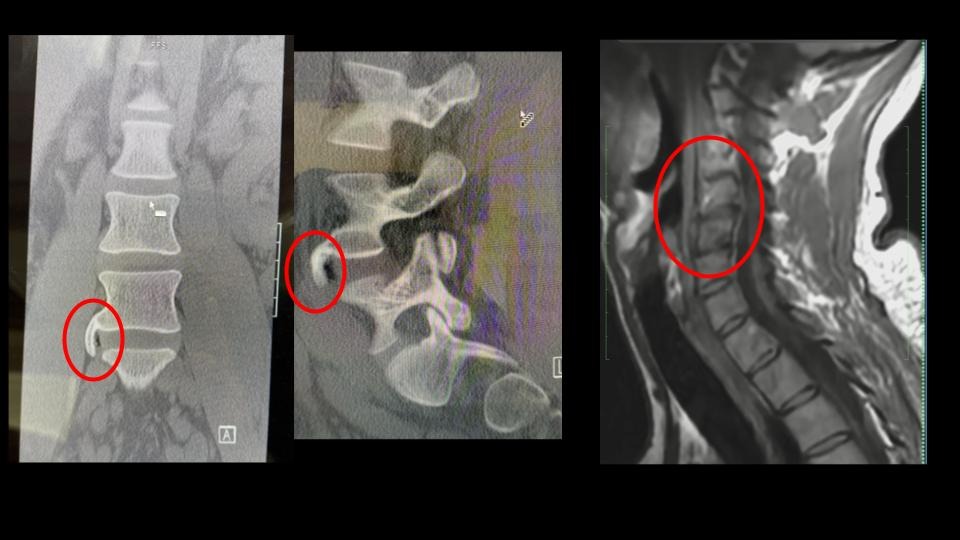

Cory is suffering from a severe spinal injury that has left him nearly bedridden for the past two months. He has a 7mm disc protrusion with osteophyte complex in his lumbar spine, a compressed sacroiliac joint, and crippling sciatic pain that radiates from his thigh down to his foot. This condition, which began in 2021, has progressively worsened, and by April 2025, the pain became so intense that he was forced to stop working completely.